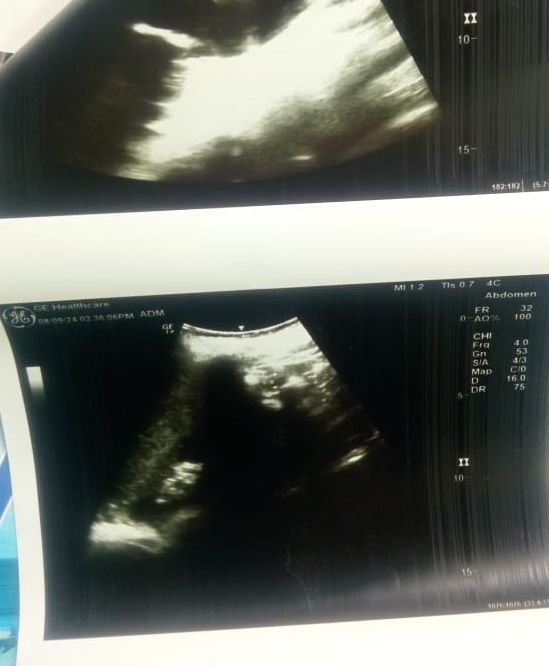

يعاني الطالب عبد الحليم رضا محمد عبد المقصود من إصابة خطيرة، نتيجة تعرضه لاعتداء من جاره بمدينة المطرية بـ محافظة الدقهلية، ويحصل على علاجه بمستشفى الزهور التابع لهيئة الرعاية الصحية ومنظومة التأمين الصحي الشامل ببورسعيد.

ذهبت الأم بنجلها لطبيب وأبلغها بضرورة نقله للمستشفى، لحاجته لجراحة عاجلة، فهرعت الأم بالصغير لمستشفى الزهور ببورسعيد، وتدهورت حالة صغيرها: حليم مبيتحركش خالص، والأطباء قالوا عمره مهيرجع طبيعي تاني، ومحاولات الإبقاء على الكلى نسبتها بسيطة، ومن المؤكد أنه سوف يتم استئصال الكلي.